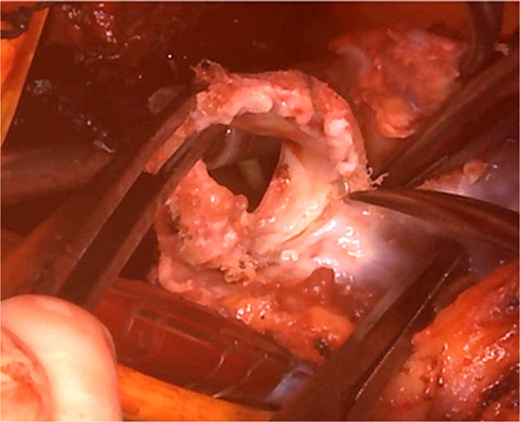

Cardiopulmonary bypass was established with ascending aorta and bicaval cannulation. The right atrium was incised, the previous TV ring was removed, and a tissue valve (MITRIS 27 mm; Edwards Lifesciences Corporation, Irvine, CA, USA) was implanted. The pulmonary artery was opened to the RVOT, and the previously implanted valve was removed (Fig. 3). The valve leaflet was not calcified but was thickened and shortened, showing a restricted opening. PVR was performed again with a 29 mm INSPIRIS valve. RVOT was closed using Gore-Tex artificial vessels graft (expanded polytetrafluoroethylene; W. L. Gore & Associates, Flagstaff, AZ, USA) for patching.

Intraoperative view: the pulmonary artery and right ventricular outflow tract opened with the previously implanted pulmonary valve explanted.